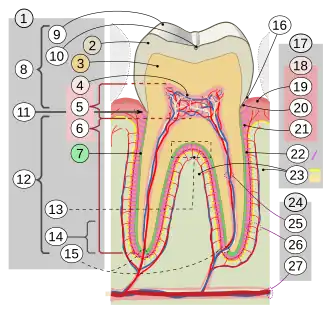

17. Periodontium

:18. Gingiva: ::19. free or interdental ::20. marginal ::21. alveolar :22. Periodontal ligament :23. Alveolar bone 24. Vessels and nerves: :25. dental :26. periodontal :27. alveolar through channel

Though mainly associated with root canal treatments, the pulp chamber's position within the crown is important in clinical practice. Several anatomical "laws" have been described to aid in locating the pulp chamber during restorative or endodontic procedures:

- Law of centrality: The pulp chamber is always located in the centre of the tooth at the level of the cementoenamel junction (CEJ).[10]

- Law of concentricity: At the CEJ level, the pulp chamber walls are concentric to the external surface of the crown.[10]

- Law of the CEJ: The CEJ is the most consistent landmark for locating the pulp chamber.[10]